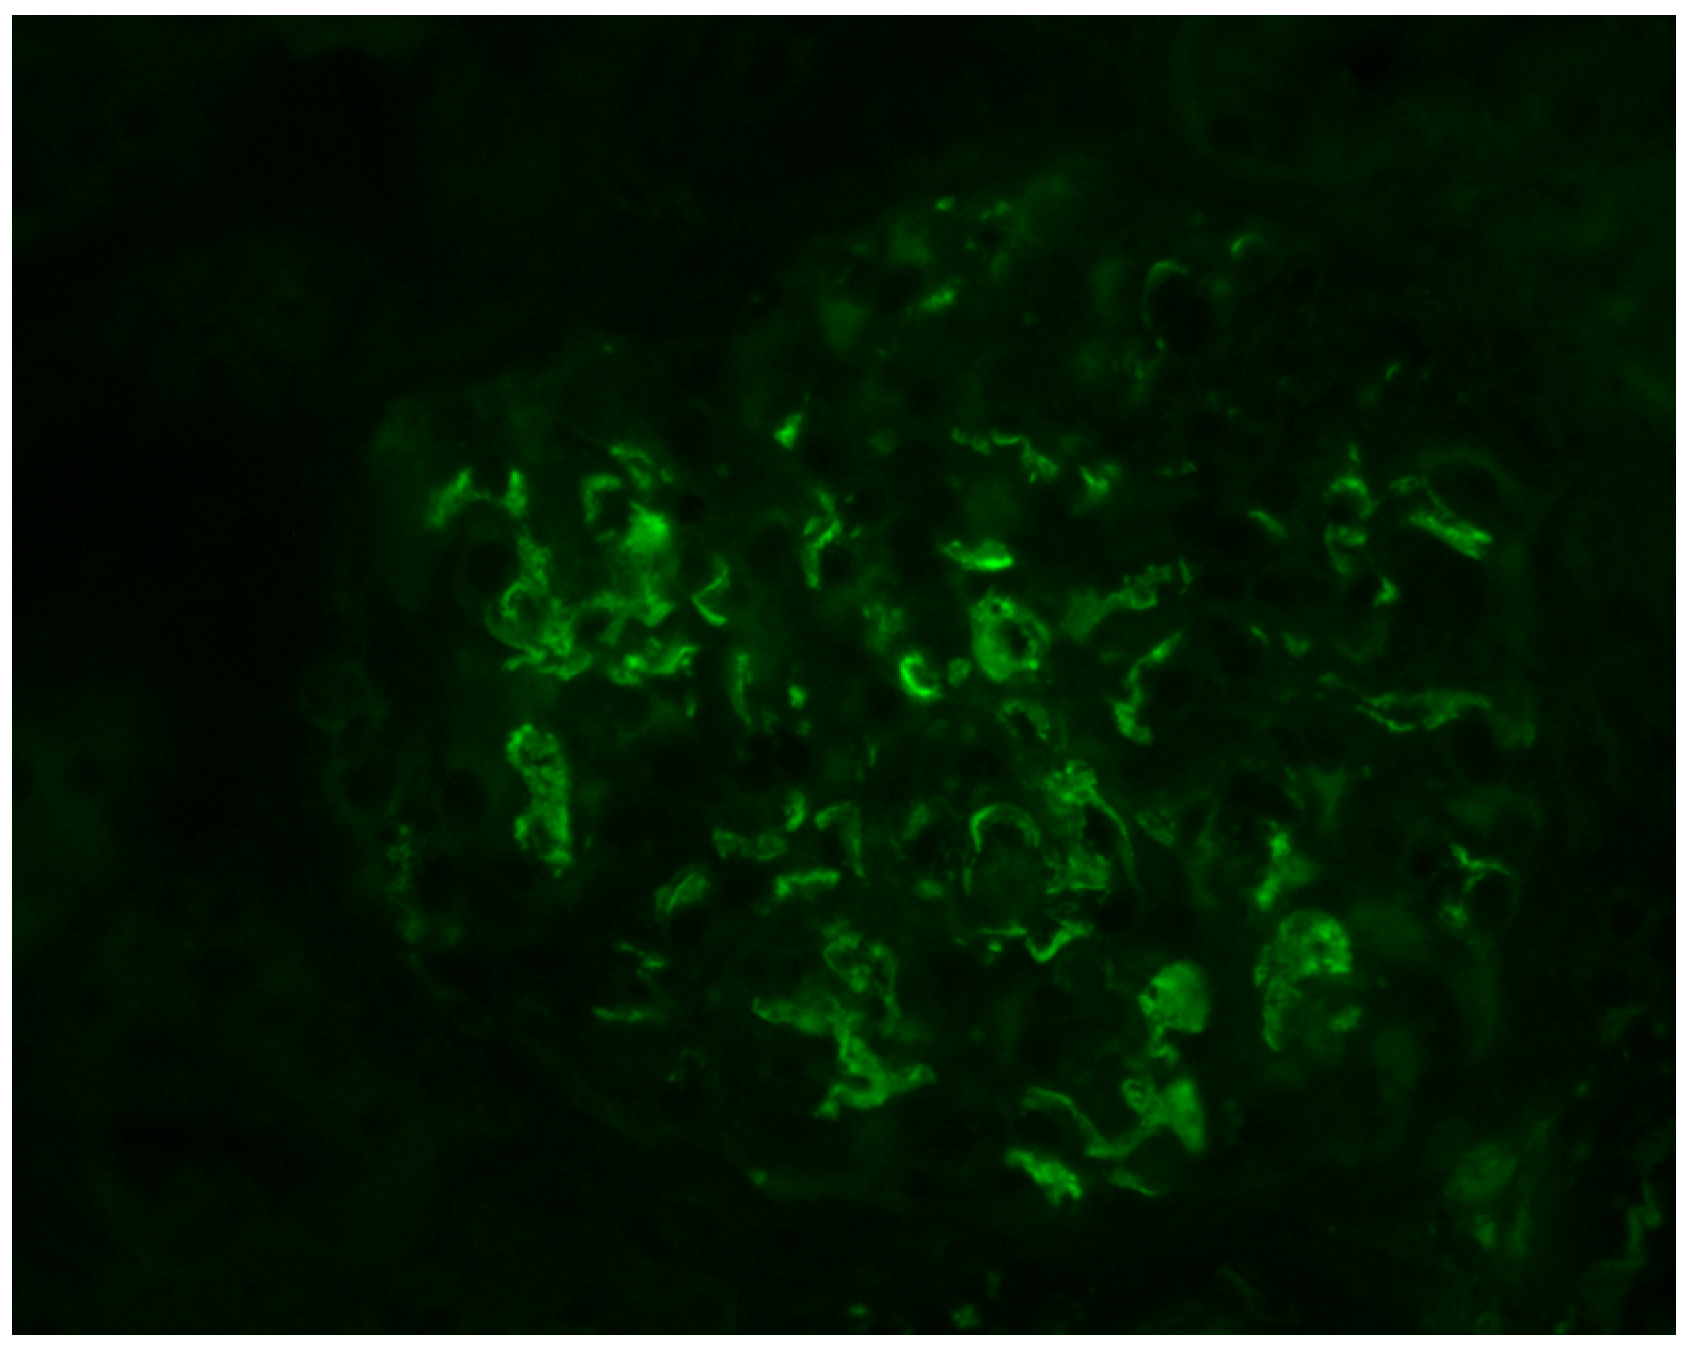

Histologically, IgAN is characterized by increase of the mesangial matrix and mesangial cell proliferation, as well as strong, dominant IgA deposition (≥2+), usually accompanied by C3 complement component, and/or IgG immunoglobulin in a lesser degree than IgA immunoglobulin and l light chain deposition, in Immunofluorescence examination. Although many cases show only mesangial proliferation, there are some cases that exhibited both mesangial and endocapillary proliferation with the influx of inflammatory cells into capillary lumens, or even extra-capillary proliferation, with glomerular crescents formation. Segmental glomerular sclerosis/scarring is also another relatively common feature, mimicking sometimes, focal segmental glomerulosclerosis, in cases showing signs of chronicity. Mesangial electron-dense deposits and a few small scattered subendothelial deposits are typically found in Electron Microscopy (EM) examination, although, in some cases, subendothelial deposits can be large. Rarely, a few small subepithelial deposits can also be recognized, although with no true membranous pattern. The tubulointerstitial department may show varying degrees of interstitial fibrosis or tubular atrophy, as well as red blood cell casts into tubular lumens. Thus, IgA nephropathy exhibits a wide spectrum of histological variability, ranging from no essential histological abnormalities to diffuse proliferative and crescentic glomerulonephritis, although most common histological patterns include focal or diffuse mesangial proliferative glomerulonephritis. Without treatment, some of the cases will progress to interstitial fibrosis and tubular atrophy, as well as glomerular scarring and loss, leading to end-stage renal disease. Taking into account the high histological diversity of the disease, but also clinical course variability, several histological grading schemes have been developed and proposed after Berger’s original disease description [12], in order to optimize therapeutic intervention and even to predict patients’ clinical course, among them, the Haas grade scheme is one of the most widely used [13]. The Oxford Classification grading scheme gained interest in the recent years and after Consensus meetings, the MEST-C score is highly recommended to be applied in every case [14,15]. In MEST-C (from Heptinstall’s Pathology of the kidney [16]), M0 or M1 indicate mesangial hypercellularity (≥4 cells in one or more mesangial areas) in ≤50% vs. >50% of glomeruli. E0 or E1 indicate endocapillary hypercellularity in zero vs. one or more glomeruli. S0 or S1 indicate segmental sclerosis in zero vs. one or more glomeruli. T0, T1, or T2 indicate tubular atrophy/interstitial fibrosis in ≤25%, 26% to 50%, or 50% of the renal cortex, respectively. C0 or C1 or C2, if cellular and/or fibrocellular crescents are absent, present in at least one glomerulus or at least 25 percent of glomeruli. Fibrous crescents are not counted toward this score (Figure 1, Figure 2, Figure 3 and Figure 4).

Figure 3.

Characteristic, mainly mesangial IgA immunoglobulin deposits, in immunofluorescence examination (IgA ×400).